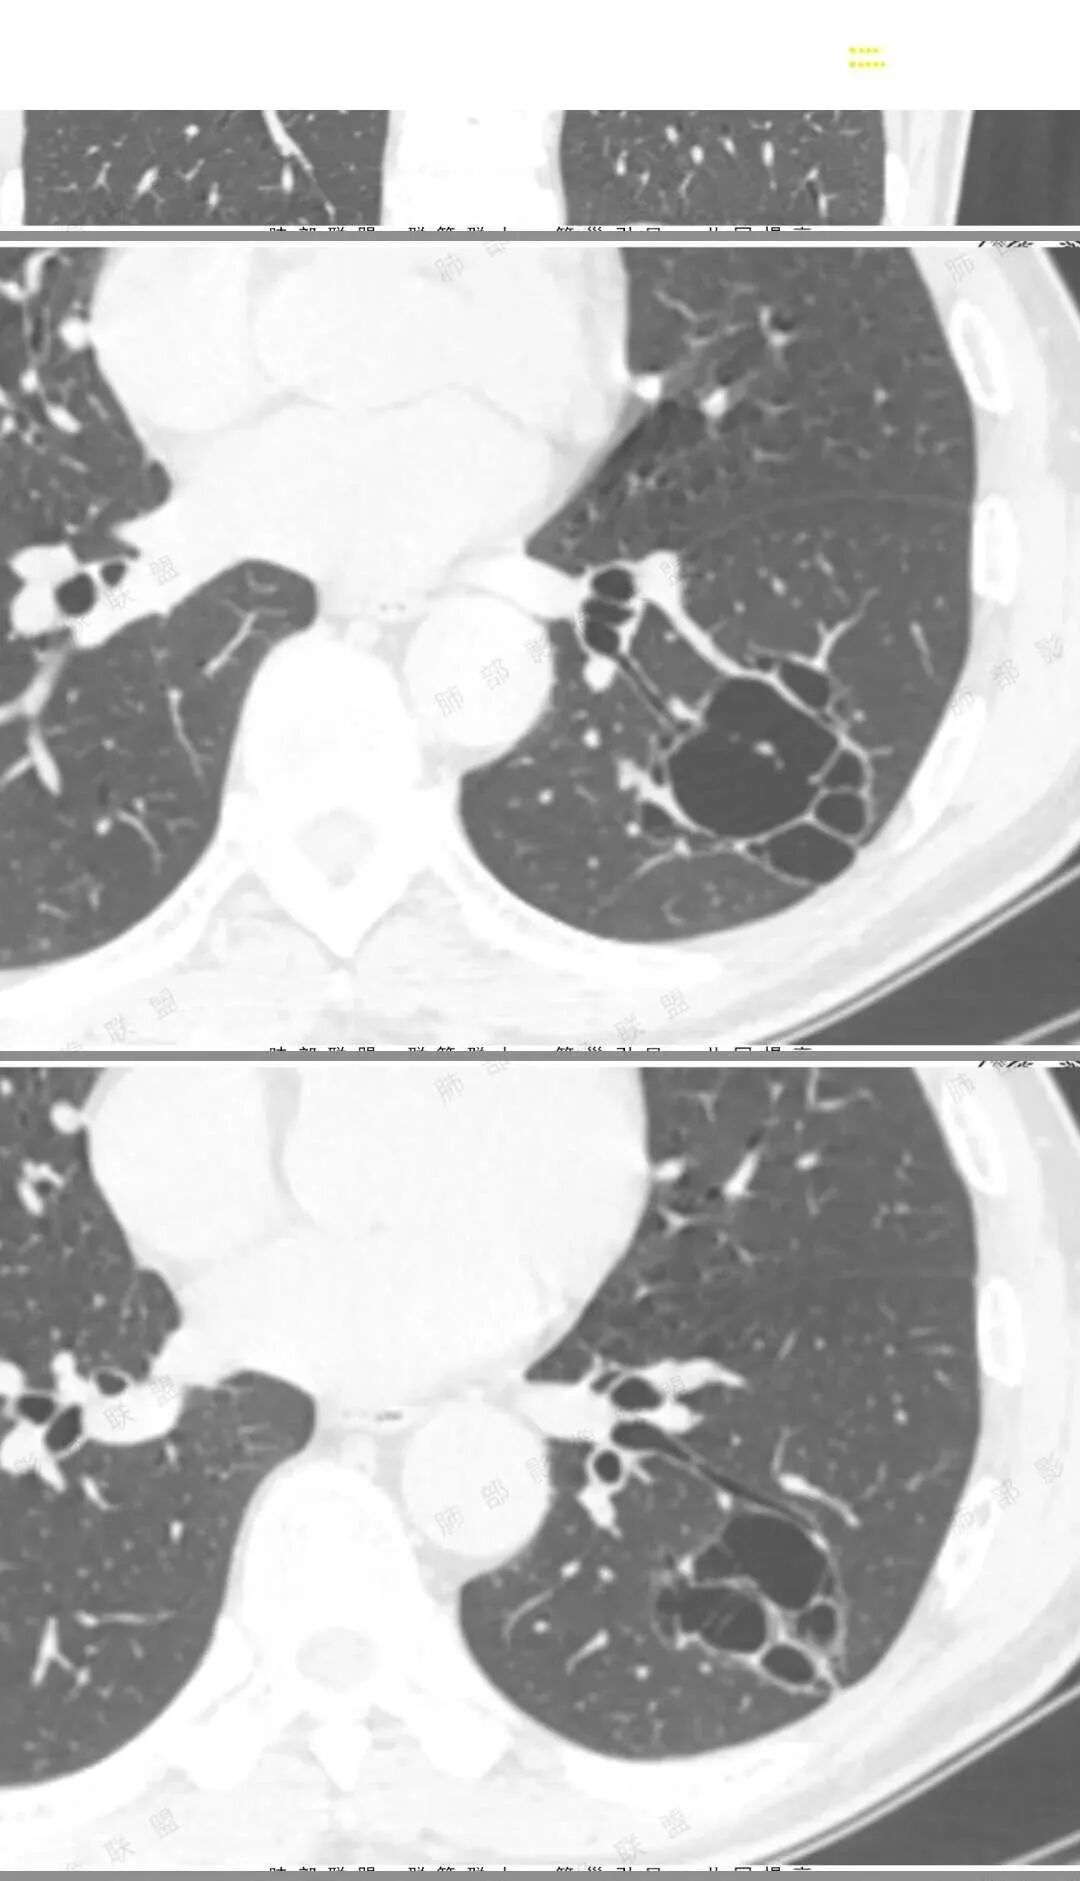

孤立性的多囊型病变伴分隔。ccam,肺隔离征,囊性肺癌,闭锁。。这是大家上面写的。看看怎么排除。血管看到肺动脉进入供血,没有感染液平,肺隔离不符合。没有代偿肺气肿,支气管没有闭锁,闭锁不考虑。那锁定ccam和肺癌。我们临床也常见是支气管畸形所致的囊。

我们看哪些内容,第1.周围有没有毛玻璃2.分隔有无粗细不均或结节,壁有无厚薄不均有无壁结节3.支气管,4.随访。

图一看到支气管堵塞,不知道是不假象

图二图三似见毛玻璃

另外分隔比较光滑似无壁结节。

目前可疑恶性,但是证据不足,毛玻璃不够,壁结节及分隔增厚结节不明显。怎么处理,要么随访,如果觉得忍不了也可以切。不会太耽误

男性,体检发现左肺阴影。影像表现:左上肺多发结节伴纤维条索影,部分钙化,左下肺囊腔样改变,内有分隔,部分分隔边缘见实性成分及GGO样改变,支气管从旁边经过,或受压,无明确进入依据。初步诊断:1、左上肺结核。2、左下肺囊腔型腺癌,诊断依据:分隔样囊腔,部分分隔有实变,边缘有GGO改变,鉴别诊断:1、囊腺瘤样畸形,分隔样囊腔要考虑,但部分分隔实变,部分伴GGO样改变成疑,最大的疑问是年龄51岁,体检发现,抽烟、饮酒30年,却无发病,可能性太小。2、囊腔性转移,单发分隔样囊腔转移少见,且需要病史支持。3、囊性淋巴瘤,一般以单发囊腔多见,分隔样囊腔型淋巴瘤罕见。4、感染,无相关临床症状及辅检支持,基本排除。

@傅昌瑜—贺州市人民医院—呼内 这个层面的GGO还是比较确定的。

@傅昌瑜—贺州市人民医院—呼内 里面的血管进一步支持恶性。但不鉴别腺癌和鳞癌,主要鉴别的,还是多囊,张力较高,囊壁较薄(实变区除外),加GGO。